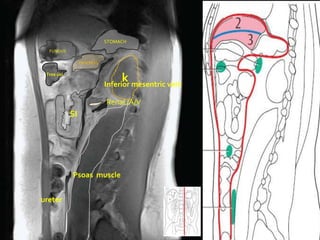

STOMACH

FUNDUS

PANCREAS

Trns col

k

Inferior mesentric vein

Renal /A/V

SI

Psoas muscle

ureter